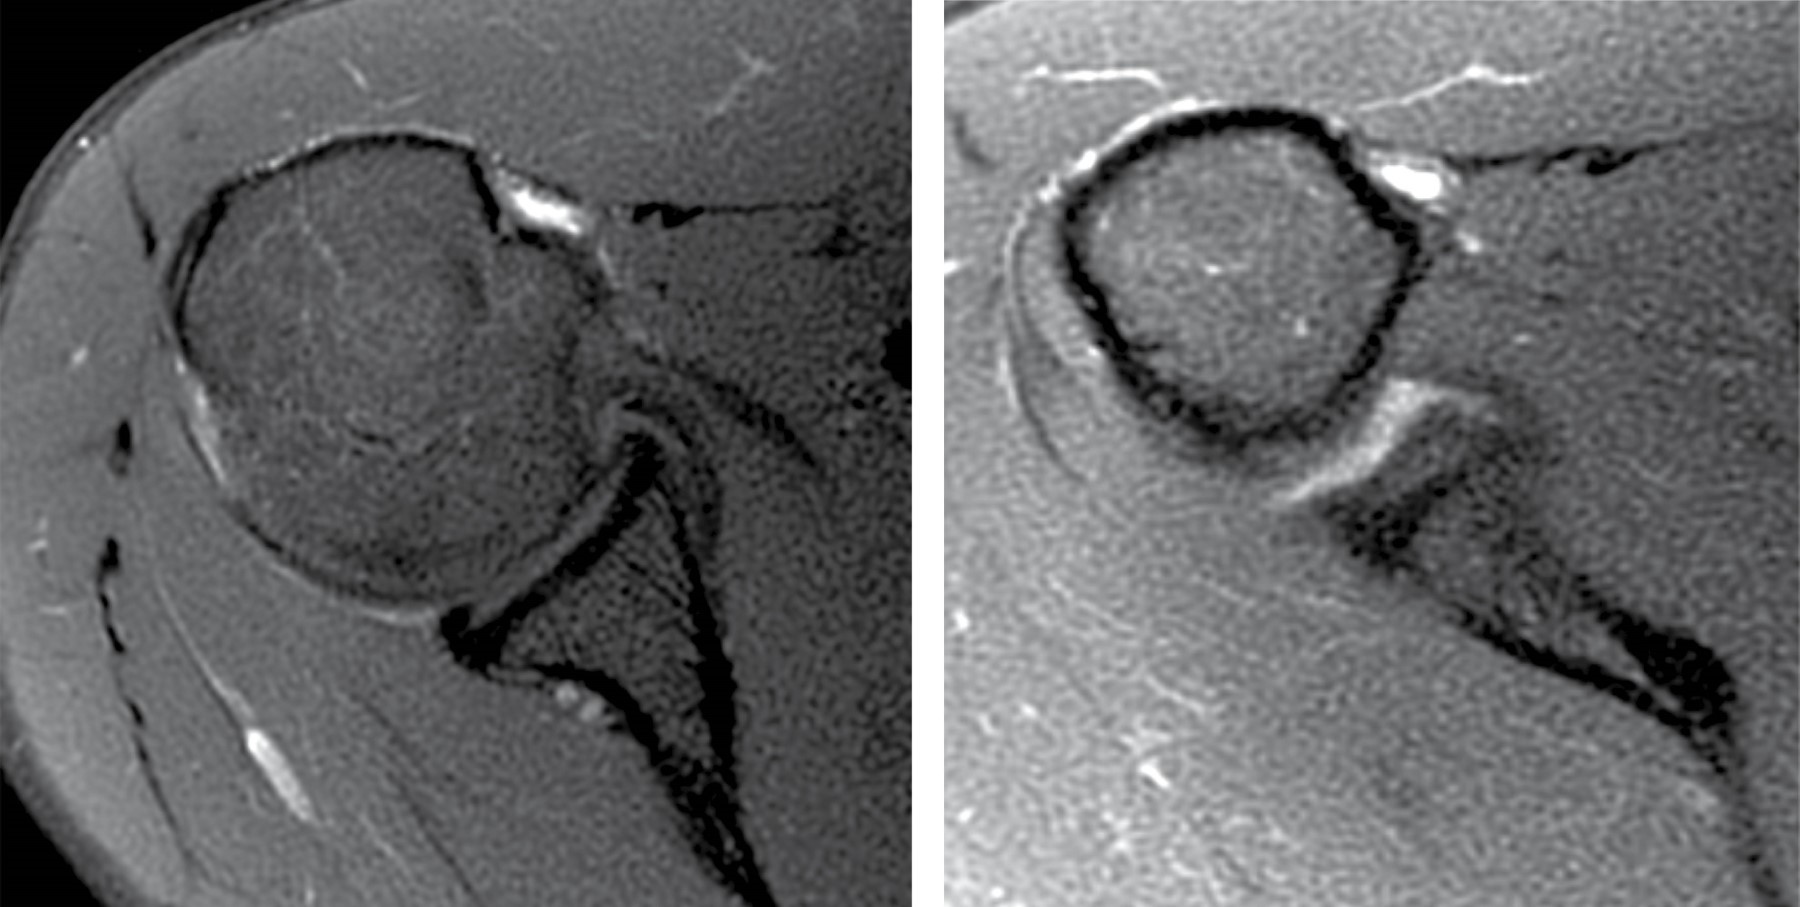

La resonancia magnética evidencia, como diagnóstico principal, una ruptura-avulsión completa de la porción larga del bíceps en su sitio de origen en el tubérculo supraglenoideo, con retracción distal de sus fibras (corredera bicipital vacía) (Figuras 1 y 2). Como hallazgo secundario, se observa tendinitis con ruptura parcial intrasustancia y de la unión miotendinosa del supraespinoso (Figura 3). Estos hallazgos explican de forma precisa la correlación clínica e imagenológica descrita en la solicitud, y demuestran la alta sensibilidad y especificidad de la resonancia magnética de hombro para la detección detallada de lesiones musculoesqueléticas.

Figura 1